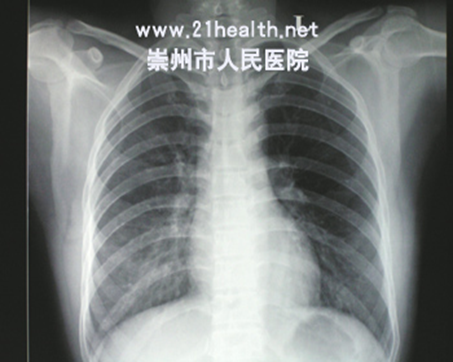

病员男性,自服克芜踪30-50ml入院,中毒后7天摄片右肺上下叶纤维化,以下叶为著(左)

两肺双肺弥漫性纤维化,中毒后12天复查胸片,病灶加重,(右)次日死亡。

百草枯中毒患者,如出现肺部损害,预后往往不发,死亡率高,故对中毒患者要密切观察肺部症状、体征,动态观察胸部X线片及血气分析,以有助于早期确定肺部病变。